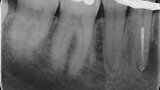

Shaping a Type V mandibular premolar with VDW.ROTATE